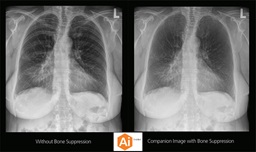

CARESTREAM Image Suite V4 MR11 has set a new standard for workflow efficiency, offering a robust set of features and functionalities to enhance clinical confidence in healthcare professionals. Using an auto-generated companion image from a single exposure, leverage a range of image processing options to increase diagnostic accuracy and enhance patient care.

Bone Suppression